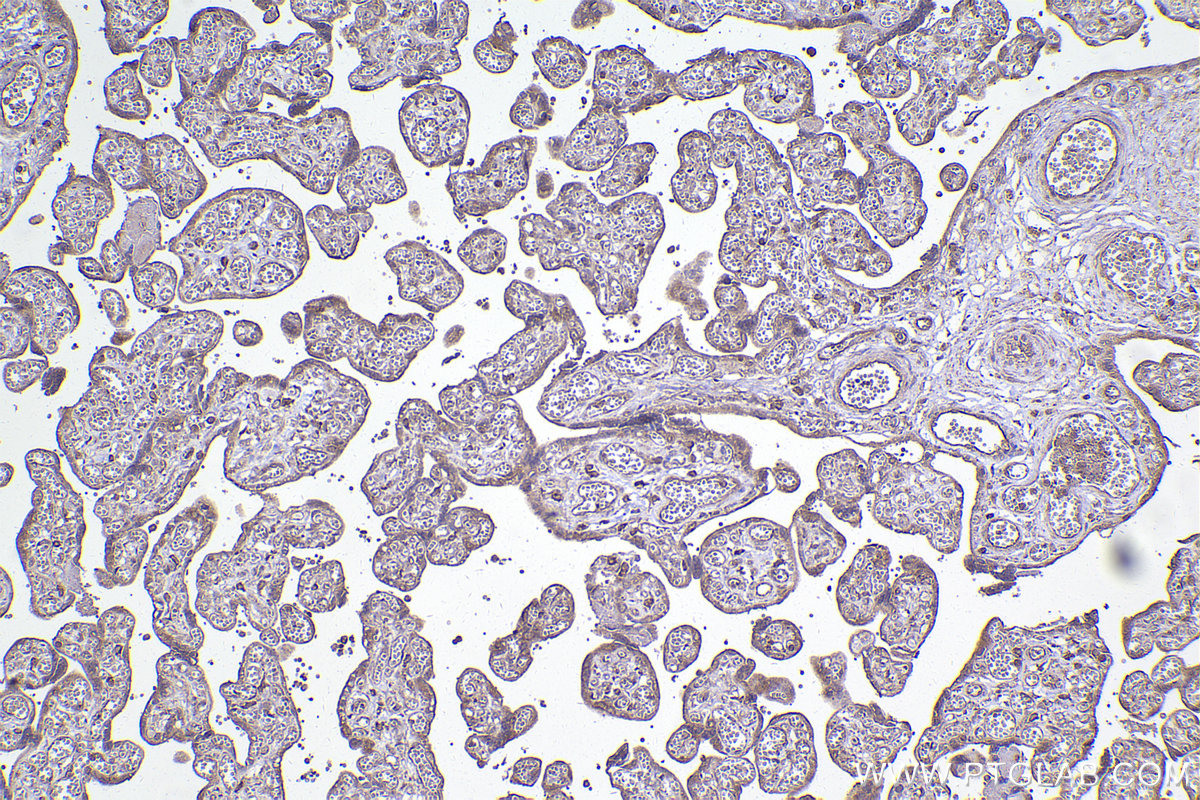

| Positive IHC detected in | human placenta tissue, human prostate cancer tissue, human skeletal muscle tissue, mouse brain tissue, mouse lung tissue Note: suggested antigen retrieval with TE buffer pH 9.0; (*) Alternatively, antigen retrieval may be performed with citrate buffer pH 6.0 |

| Immunohistochemistry (IHC) | IHC : 1:1000-1:4000 |